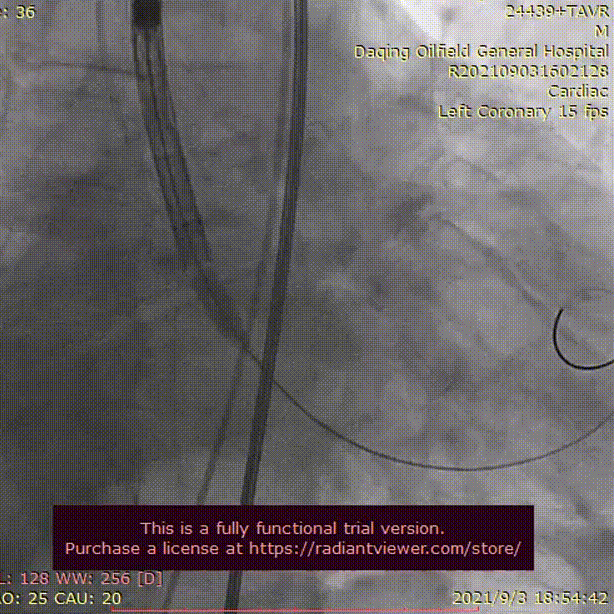

LM术前

LM支架置入术后